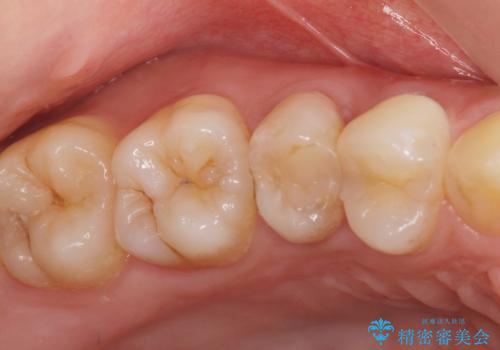

銀歯が取れた 中が虫歯 セラミックインレーに

- 矯正治療中に銀の詰め物が取れたとのことでした。

中が虫歯になっていたため、虫歯を除去し、セラミックインレーにやり変えました。

- emax プレスインレー 7万円費用は治療当時の料金となります

詰め物が取れてくる場合は、中が虫歯で取れる場合があります。

その際は元の詰め物をつけることはできず、インレーのやりかえとなります。